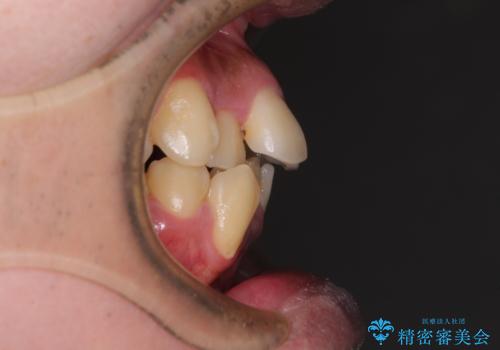

上下左右の犬歯が八重歯になっており、口元にもやや突出感があるため、上下左右の小臼歯4本を抜歯し、ワイヤー装置にて矯正治療を行うこととしました。

右上第一小臼歯は歯根癒着により移動せず、左上第二小臼歯は移動はするものの非常に動きが鈍かったため、抜歯したスペースを閉じるまでに非常に時間がかかってしまいました。